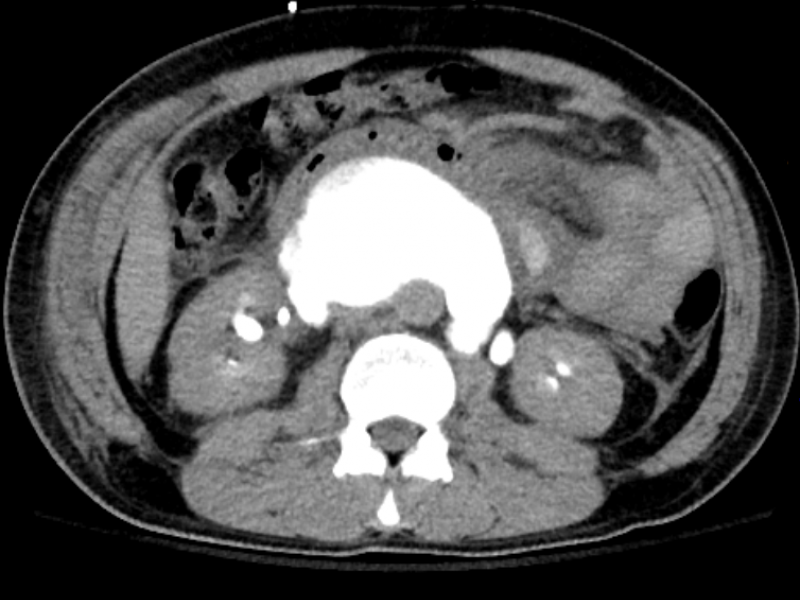

A 44 yo M with a remote history of testicular cancer and